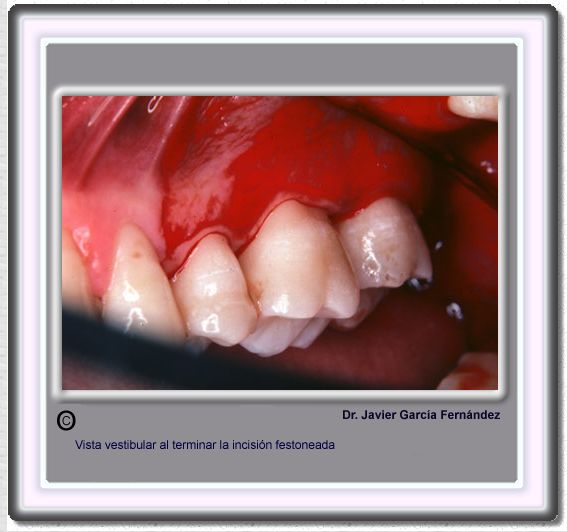

image 492